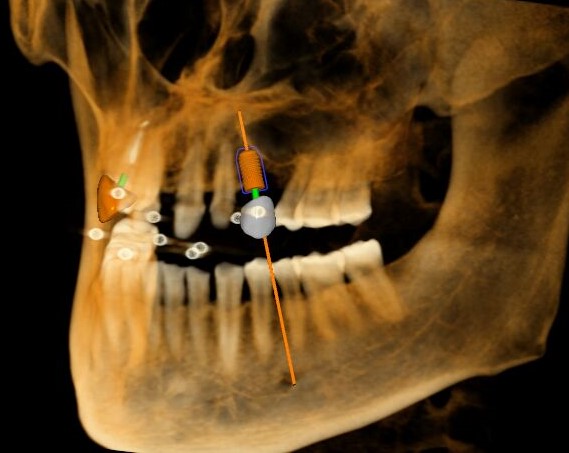

觀察患者CT,可看出患者有上頜竇粘膜囊腫,粘膜囊腫為竇內(nèi)腺體阻塞所致,視情況可有手術(shù)摘除和不予處理兩種方法,此次患者拒絕手術(shù)摘除,故需規(guī)避上頜竇位置。

根據(jù)患者CT顯示,使用種植導(dǎo)航軟件設(shè)術(shù)前手術(shù)方案??紤]到患者拒絕手術(shù)摘除上頜竇囊腫等因素,此次手術(shù)選用了Straumann骨水平4.10*8.0mm的植體,植體末端位點設(shè)計距上頜竇底壁2mm處的同時兼顧種植方向和修復(fù)間隙,來達(dá)到理想的效果。

導(dǎo)航下精細(xì)分配修復(fù)間隙,精細(xì)規(guī)劃植入方向,避開上頜竇底,精確植入

從術(shù)后CBCT顯示可以看出,手術(shù)操作中完美地避開上頜竇底,并兼顧了正確的種植方向和修復(fù)間隙